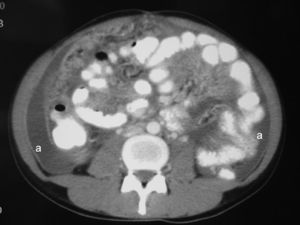

Presentamos el caso de una mujer de origen español de 26 años, sin antecedentes familiares ni personales de interés, que acude al servicio de urgencias de nuestro hospital por lumbalgia de 1 mes de evolución que no mejora con tratamiento con antiinflamatorios no esteroideos y que, en la última semana, concurren distensión abdominal, progresiva, indolora y fiebre de hasta 38°C de predominio vespertino. No refiere otra clínica digestiva ni síndrome general. El examen abdominal muestra ascitis a tensión y molestias abdominales difusas sin signos de irritación peritoneal. Los estudios analíticos, las radiografías de tórax y abdomen resultaron normales. Se procedió a una paracentesis evacuadora (negativa para células malignas, líquido ascítico, con características de trasudado y con adenosindesaminasa [ADA] de 2,7U/l). La tomografía computarizada (TC) abdominal informó de implantes tumorales difusos epiploicos y mesentéricos, ascitis masiva y quistes de 3cm en los ovarios (figs. 1 y 2), todo ello indicativo de carcinomatosis de posible origen ginecológico. Los marcadores tumorales fueron normales, excepto el CA 125 que tenía un valor de 517U/ml. La paciente fue intervenida, a los 15 días del ingreso, mediante laparoscopia de forma programada, en que se objetivó un gran bloqueo de asas intestinales e implantes de carcinomatosis en toda la zona, por lo que se consideró inviable una cirugía con intención curativa y se procedió a la toma de múltiples biopsias de implantes peritoneales y en el epiplón mayor. La anatomía patológica fue informada como peritonitis necrosante granulomatosa de origen tuberculoso. La evolución postoperatoria fue favorable y se le dio de alta al octavo día postoperatorio con tratamiento antituberculoso basado en isoniazida, pirazinamida, rifampicina y etambutol durante 6 meses. La paciente siguió en estudio y control, de forma ambulatoria, por el servicio de medicina interna, mediante pruebas radiológicas, broncoscópicas, con lavados y cepillados del árbol bronquial, determinaciones serológicas de los virus hepáticos y de la inmunodeficiencia humana, pruebas analíticas para valorar la función hepática, el ácido úrico, etc., sin objetivarse otros focos de tuberculosis, etiologías inmunosupresoras ni efectos secundarios por la medicación. La paciente tuvo el alta definitiva a los 12 meses. En la actualidad, y tras tantos meses de seguimiento, se encuentra asintomática y no precisa tratamiento alguno.

La ecografía y la TC evidencian hallazgos inespecíficos, el más frecuente es la ascitis, como sucedió con nuestra paciente. El análisis de la ascitis puede ser un exudado con predominio linfocítico1 o, como sucedió con nuestra paciente, un trasudado con cultivos negativos para BAAR. No obstante, algunos autores han publicado resultados de cultivos positivos en casos con paracentesis de más de 1l tras su centrifugado3. La ADA es una enzima degradadora de purinas necesaria para la maduración y la diferenciación de las células linfocíticas. La actividad de la ADA en líquido ascítico se ha propuesto como un método útil para la detección de la tuberculosis. Un metaanálisis de 12 estudios prospectivos, con 264 pacientes, encontró que el valor de la ADA tenía altas sensibilidad (100%) y especificidad (97%), con valores de corte entre 36 y 40U/l, el valor óptimo de corte fue 39U/l6. Hay falsos positivos en casos de cirrosis, peritonitis bacterianas espontáneas e infecciones por Chlamydia. Si la ADA es mayor de 50U/l, los falsos positivos son casi inexitentes4. Nuestra paciente presentaba una cifra de ADA en el líquido ascítico normal, 2,7U/l (normal, hasta 45U/l).